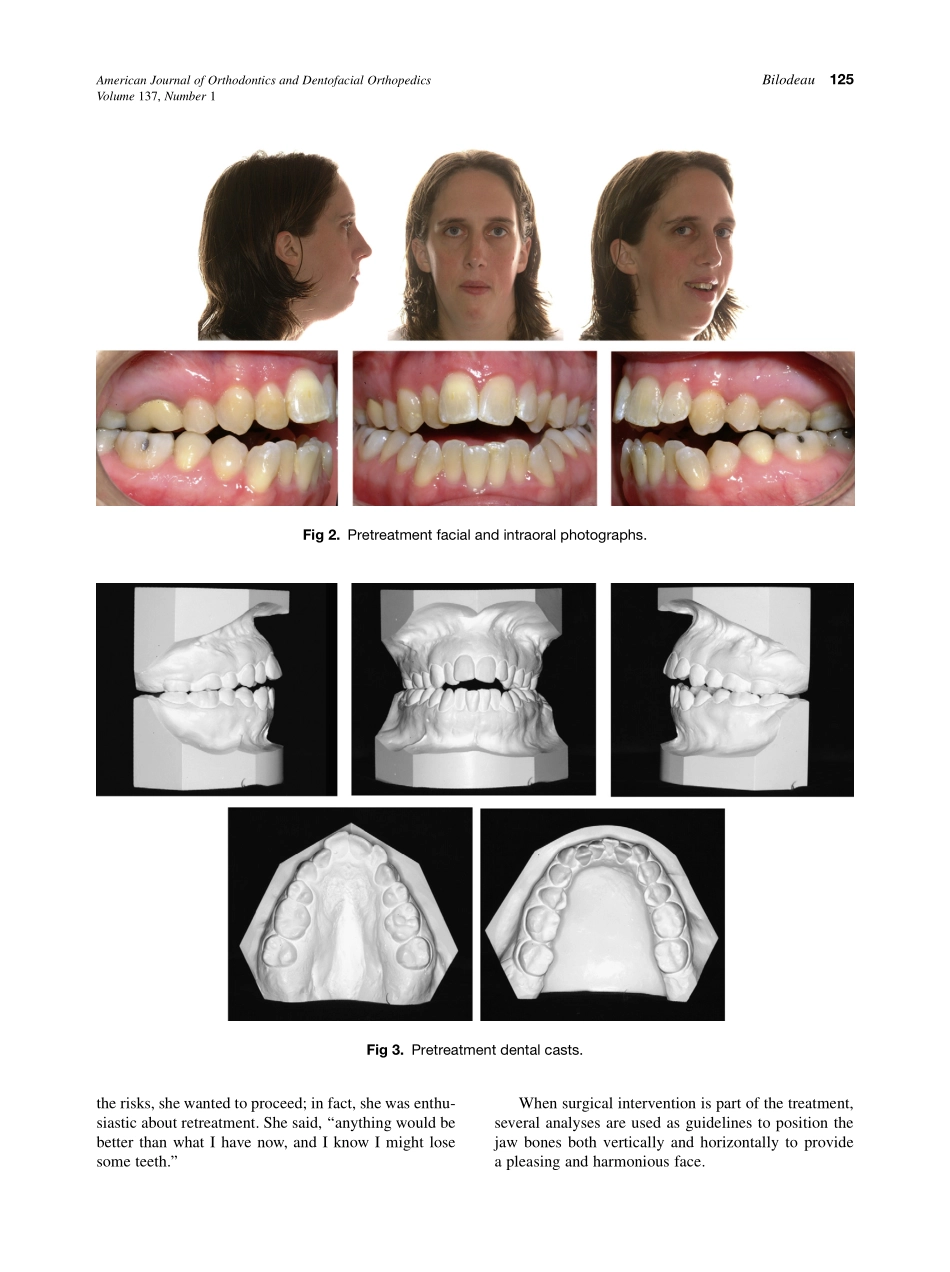

CASEREPORTRetreatmentofapatientwithMarfansyndromeandsevererootresorptionJohnE.BilodeauSpringfield,VaThiscasereportdescribestheretreatmentofapatientwithMarfansyndromewhoseearlierorthodonticandsurgic...